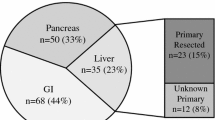

Nineteen patients (7 women and 12 men; age range 26–82 years, mean 60.3 ± 13.6) were enrolled for comparison of 68Ga-DOTA-NOC PET/CT and OCT in imaging NETs. Patients were referred for tumor staging, detection of somatostatin receptors prior to peptide receptor radionuclide therapy (PRRT), and for evaluation of response to therapy. The tumors included well-differentiated endocrine carcinoma and poorly differentiated endocrine carcinoma: carcinoid (n = 8), pancreatic NE tumor (n = 9), and NE carcinoma of unknown origin (n = 2). Patient information, together with pathologic diagnosis based on World Health Organization criteria, is shown in Table 1.

Clinical details of the 19 patients are reported in Table 1. Positive findings of tracer uptake in at least one lesion were seen in all patients both on 68Ga-DOTA-NOC and OCT images, as expected since only subjects with previous positive OCT SPECT imaging were included. Findings on 68Ga-DOTA-NOC PET/CT were overall more numerous and more distinct, with much better tumor to background contrast and less image noise. Findings of both imaging modalities are listed for individual patients and regions, together with comparison with morphological data in Table 2, and summarized by regions for all patients in Table 3.

Similar pathological tumor sites were visible on both 68Ga-DOTA-NOC and OCT in a total of 41 regions in all 19 patients. Additional foci of pathological uptake were seen in 21 regions on 68Ga-DOTA-NOC only and in 15 regions on OCT only. Foci of tracer uptake were observed in the liver, pancreas, bone, lymph nodes, digestive tract, as well as a few additional findings in other parts of the body including soft tissue, brain, thyroid, and tonsils. Differences between the two imaging modalities did not appear to be more prevalent in specific regions (see Table 3). 68Ga-DOTA-NOC uptake in tumor foci was often very intense, and this is reflected in the maximum SUV which ranged from 2 to 165 (see Table 2). As seen from Tables 2 and 3, many findings were comparable in both imaging modalities, though even in those regions where identical tumor foci were described, foci of enhanced tracer uptake were generally clearer on the 68Ga-DOTA-NOC images, and with the assistance of co-registered CT for all scans, anatomical localization of findings was easier and more precise. Examples of images showing comparable findings in both modalities, but illustrating greater clarity and contrast with 68Ga-DOTA-NOC, are shown in Figs. 1 and 2.

Verification from anatomical imaging (CT, MRI, or US) was found for 31 of the 41 (76%) regions with concordant 68Ga-DOTA-NOC and OCT findings. CT, MRI, or US verification was also found for 15 of 21 (71%) regions seen on 68Ga-DOTA-NOC only, suggesting that most if not all of these findings were indeed true positive findings. On the other hand, confirmation was only available for 4 of 15 (27%) regions, with findings seen only on OCT, most of which were faint and poorly delineated and thus could not be clearly and unambiguously identified as tumor foci.

The additional foci of enhanced 68Ga-DOTA-NOC uptake had implications for disease staging in 4 of 19 patients. There were also implications for patient management in three patients, resulting in the referral of two patients for PRRT and more intensive follow-up in the third patient.

Our series included patients with carcinoid, pancreatic tumor, and metastatic NE tumor with unknown primary. Differences in findings between the two imaging modalities appeared throughout and did not depend on the type of disease. Likewise, tumor foci were seen throughout the body in the liver, pancreas, bone, lymph nodes, digestive tract, and a few other locations, and in all organs involved, there were findings that were concordant as well as some that were discordant between the PET and SPECT imaging modalities. This is in contrast to the findings with 68Ga-DOTA-TOC in the study of Buchmann et al. [8] who found discrepancies between 68Ga-DOTA-TOC and OCT in the lung and skeletal system, but not in the liver and brain. However, only one patient in our small series had brain involvement, and none had lung manifestations.